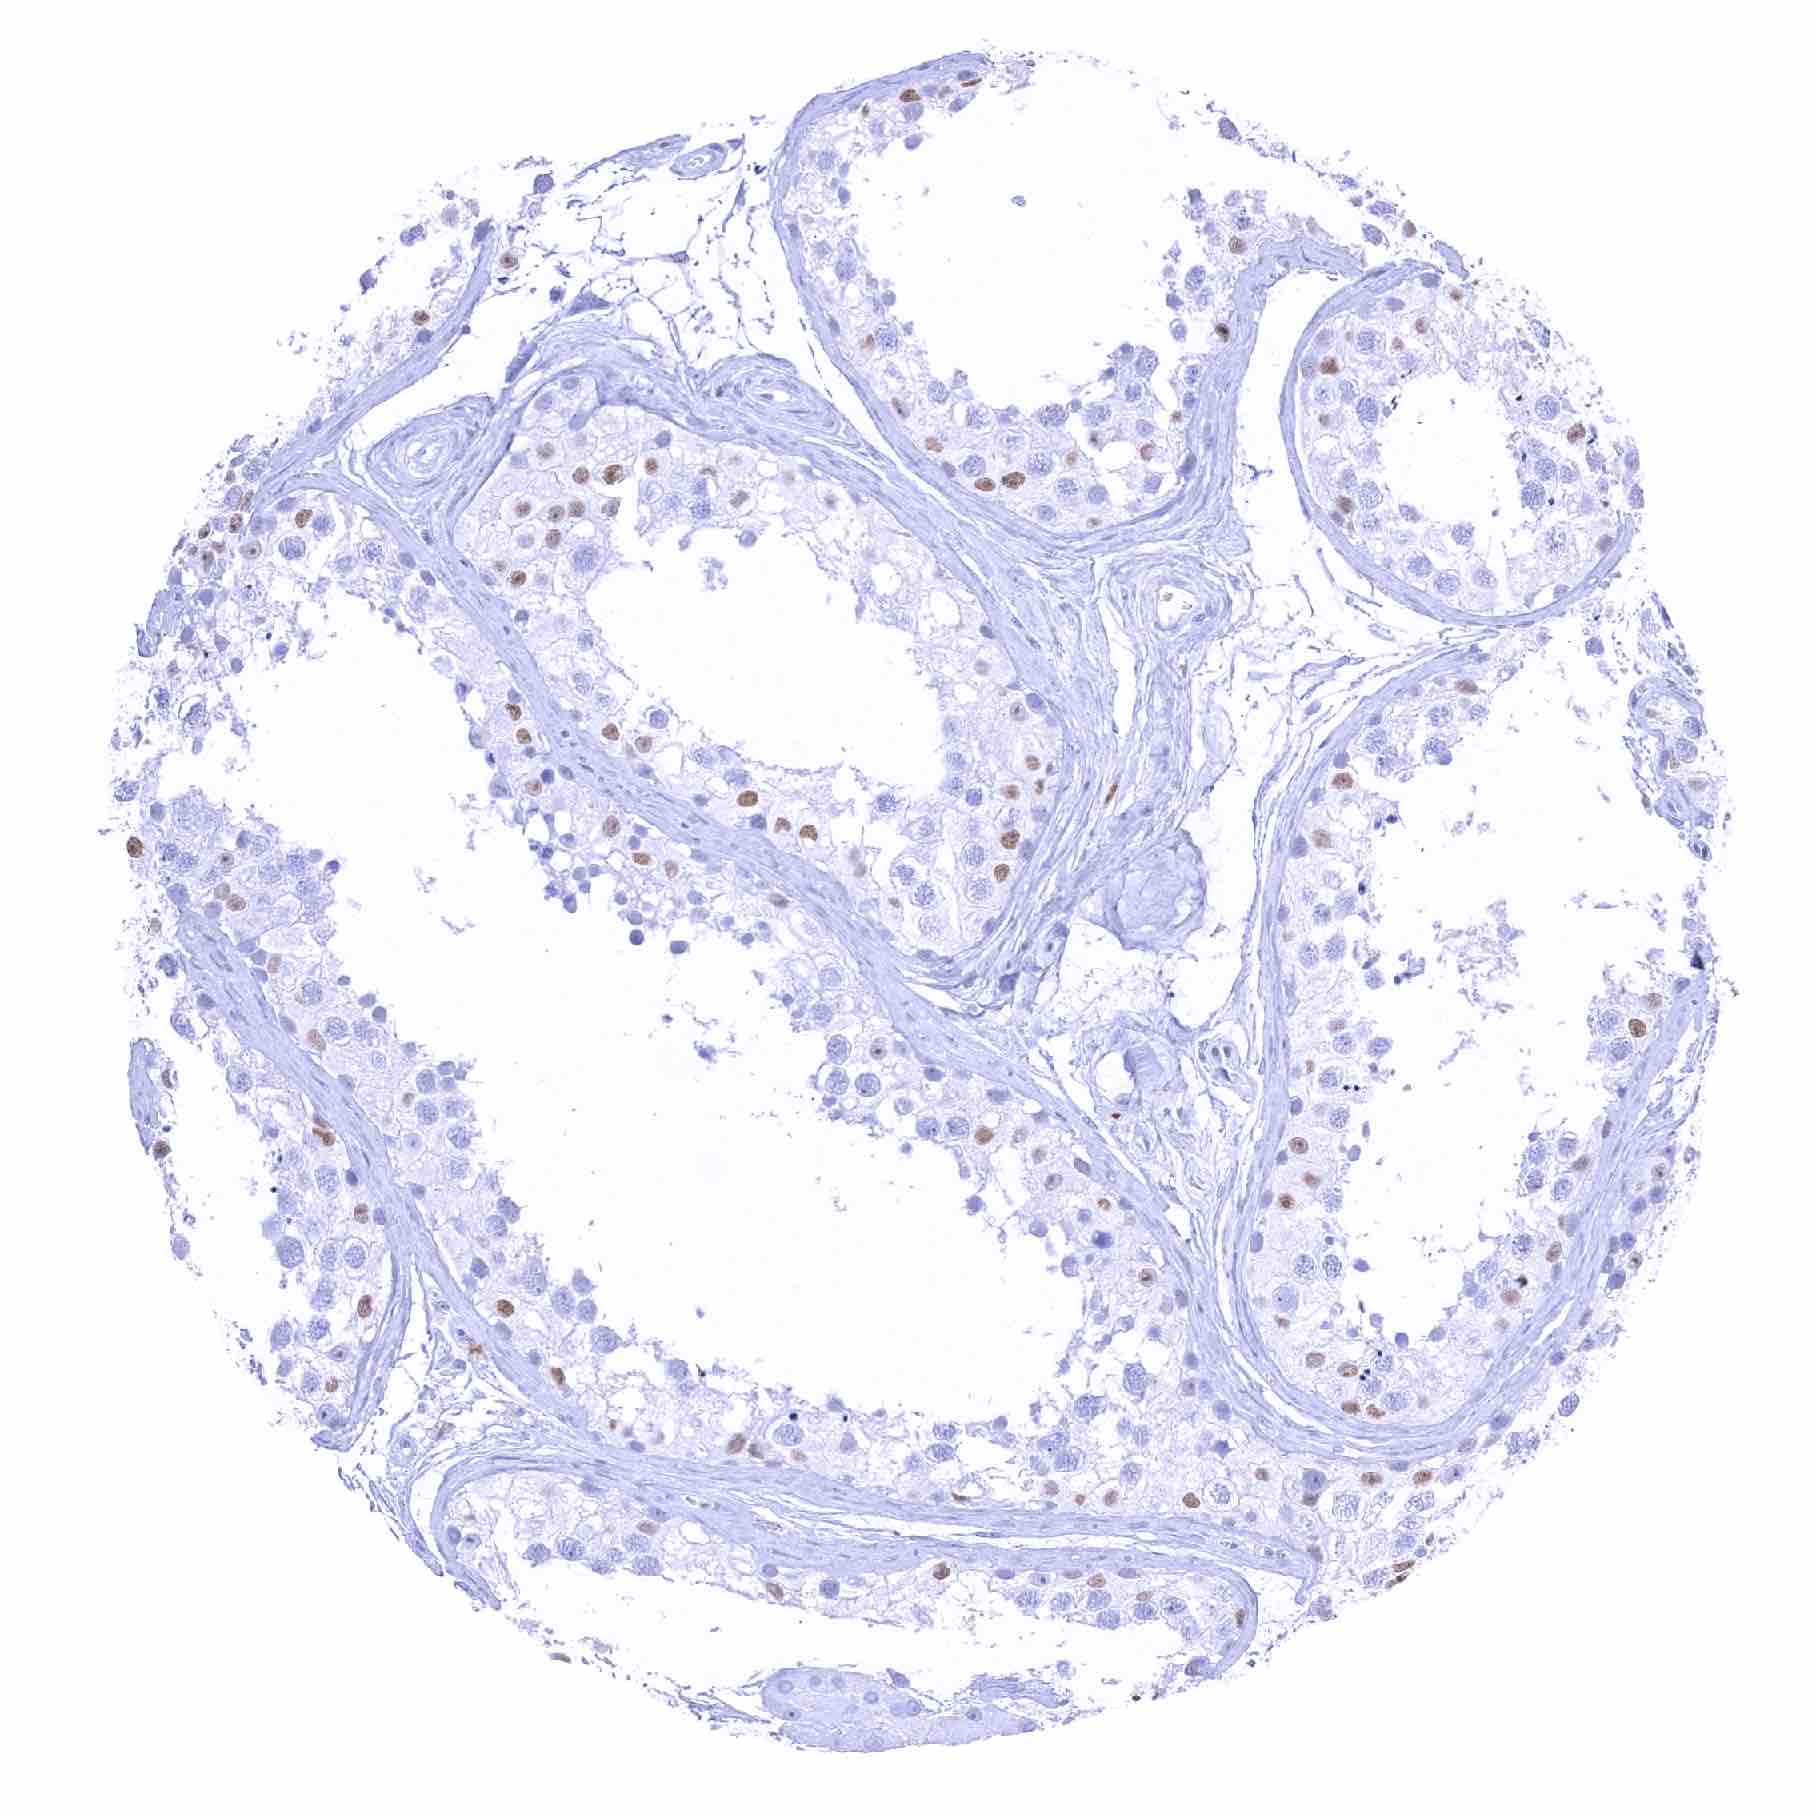

Testis – Weak to moderate SOX2 positivity of spermatocytes